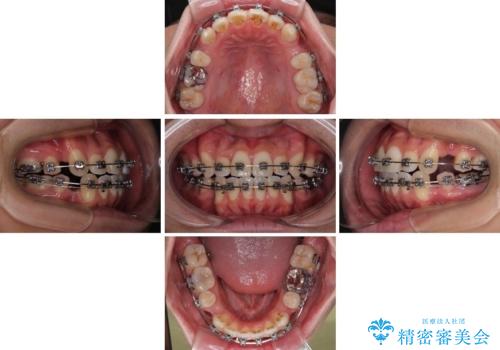

- 口元の突出感が強く、口が閉じにくいことを主訴として来院された患者さんの症例をご紹介します。

前歯部の叢生(デコボコ)も認められ、歯がきれいに並ぶためのスペースが不足している状態でした。

これらの問題を総合的に改善するため、上下左右の第一小臼歯を計4本抜歯し、スペースを確保する治療計画を立てました。

抜歯したスペースを活用して前歯を後ろへ下げることで、口元の突出感を大きく改善。

奥歯の噛み合わせがずれている「シザーズバイト」を適正に整えることで、見た目だけでなく機能性も向上し、安定した咬合が獲得できました。